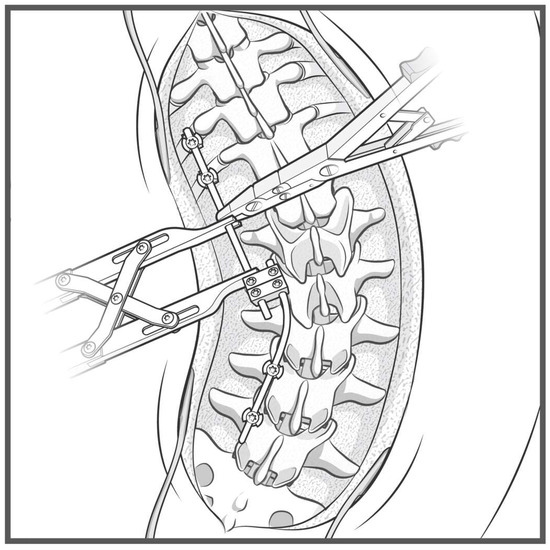

A detailed surgical technique guide by Buchowski et al. in 2007 describes temporary internal distraction in a broader context and highlights important considerations, such as preoperative surgical planning, patient positioning, and placement of proximal and distal anchor points [4]. However, this report aims to focus on the placement and configuration of spinal rods for internal distraction or compression utilizing the construct-to-construct technique. To set up the construct-to-construct configuration, one rod is attached to the proximal anchor points and a second rod to the distal anchor points. There should be at least two (or more) anchor points at the proximal and distal ends to set up this technique. This helps prevent plowing of pedicle screws by distributing the distractive and compressive forces across several motion segments along the spine. These rods are joined by one or two lateral domino connectors to complete the construct-to-construct setup. The more overlap of the rods, the more “runway” there is to apply distraction (Figure 1). Conversely, the less overlap that exists between these two rods, the more “runway” there will be to apply compression (Figure 2). If internal distraction is desired, this construct-to-construct configuration will need to be set up on the concavity of the scoliosis curve. Alternatively, the construct-to-construct configuration will need to be set up on the convexity of the scoliosis curve if internal compression is needed. Distraction or compression is then applied to these rods in a serial, “click-by-click” fashion after loosening the ipsilateral set caps on the domino connectors. Rod grippers may be used to distract or compress against instead of utilizing pedicle screw tulips in order to reduce loosening of the anchor points. After the desired amount of deformity correction is achieved, the set caps on the domino connectors are tightened to hold the correction.

Figure 1.

Sawbone model utilizing a construct-to-construct internal distraction technique showing the greater overlap of the rods across the lateral domino connectors, the more “runway” there is to apply distraction.

3.2. Internal Distraction on the Concavity of a Major Scoliosis Curve

The first clinical scenario where the construct-to-construct internal distraction technique may be useful is during surgical correction of severe scoliosis curves > 90 degrees. This technique is most effective in large, flexible sweeping curves that involve multiple spinal levels. Sharply angulated and rigid curves with high-deformity angular ratios (DAR) are better managed with three-column osteotomies [5,6]. We prefer placing our anchor points to set up the construct-to-construct internal distraction configuration early in the procedure. The viscoelastic environment of the spine will permit gradual sequential distraction to relax soft tissues and make them more compliant with progressive correction techniques. In severe major curves, it is often challenging to get the rods parallel into the domino connectors. A combination of rod bending and handling with a rod gripper helps achieve the contour necessary to set up the construct-to-construct configuration. After initial distraction is performed on the concavity of the scoliosis (Figure 3), the remainder of the spine should be exposed in a subperiosteal manner. Posterior column osteotomy releases will gradually enhance deformity correction by removing the posterior spinal elements, so long as the anterior columns of the corresponding motion segments are not fused together. Small and repetitive distraction maneuvers are applied over the course of the surgery until appropriate correction is achieved and final fusion may be performed. Upgoing rib hooks sometimes provide an excellent option for internal distraction (Figure 4 and Figure 5). If adequate correction is not achieved or there is concern about risk of neurological injury due to intraoperative neuromonitoring (IONM) changes, then a staged procedure may be performed at a later time.